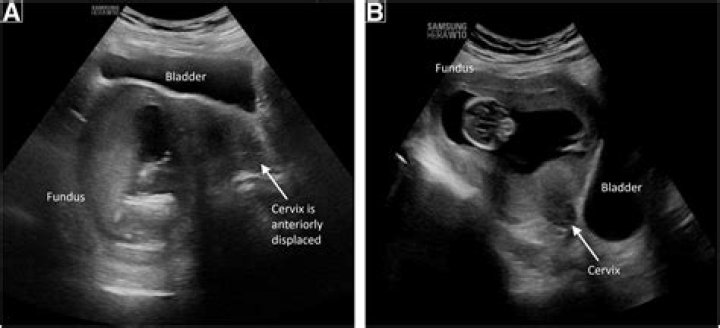

The positioning of the uterus can change from anteversion to retroversion due to the filling of bladder or during pregnancy; however, changing from retroverted to anteverted position without prior pregnancy or endometriosis is rather uncommon.